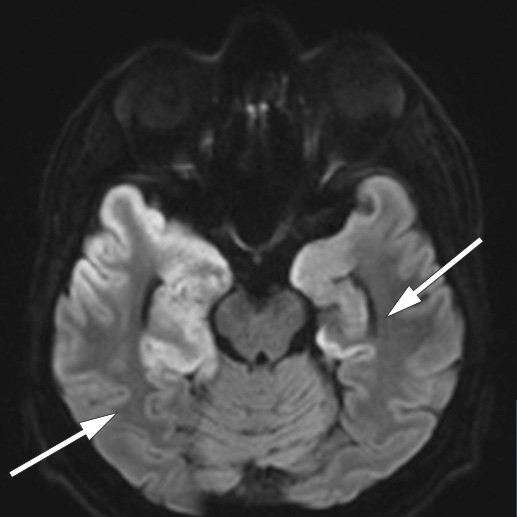

Denne viste patologisk langsom bakgrunnsaktivitet og utbrudd av deltaaktivitet i temporale regioner. Funnet var forenlig med encefalitt (6, 7). MR-undersøkelse av hodet, som ble utført seks dager etter innleggelsen, viste utbredte forandringer temporalt, inkludert i hippocampus, hvilket er typisk for herpesencefalitt (8) (figur 2, figur 3a).

En uke etter oppstart med immunglobulinbehandling ble det bekreftet høyt titer av antistoff mot NMDA-reseptor i pasientens spinalvæske. En ny cerebral MR-undersøkelse tatt fire uker etter den første, viste økende høysignalforandringer temporalt bilateralt. Dette funnet er ikke spesifikt for verken herpesencefalitt eller autoimmun encefalitt (11).

Tilstanden stabiliserte seg etter noe tid, og man forsøkte rehabilitering i flere omganger, men pasienten gjenvant aldri tilstrekkelig funksjon til å kunne bo hjemme. Han bor nå i omsorgsbolig med stort oppfølgingsbehov. En ny MR-undersøkelse 4,5 måneder etter symptomdebut viste omfattende skade i temporallapper (figur 3b).

Hos vår pasient var det nok allikevel den virale encefalitten som ga størst permanent skade (figur 3a og b).